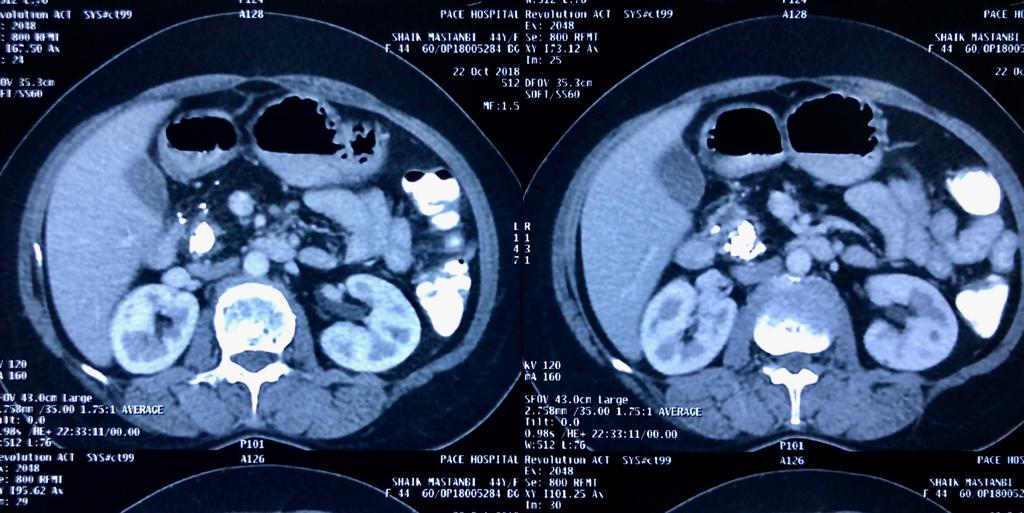

Total pancreaticoduodenectomy with splenectomy done for a 45 yr female with main duct

Total pancreaticoduodenectomy with splenectomy done for a 45 yr female with main duct IPMN with invasive mid-body cancer with bilateral polycystic kidneys. Her EUS, ERCP and fluid cytology , fluid CEA, serum CA19 -9 were all suggestive and a PET showed high uptake in her solid .She is doing well post op but planned for adjuvant CT Rt as had breached capsule and encased splenic vein. Total pancreaticoduodenectomy was frowned upon as a high morbidity surgery due to severe exocrine and endocrine insufficiency with brittle diabetes and ulcerogenicity due to complete loss of pancreatic bicarbonate secretion. But in recent years with easy availability of enzyme supplements, CGM (continuos glucose monitoring devices), insulin pens and long acting PPI the long term QoL of these patients is comparable with partial pancreatectomy patients